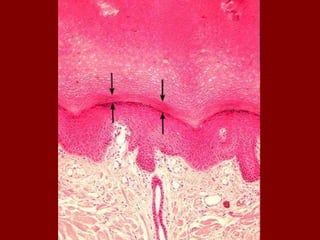

Acne

• For reasons not

completely understood,

follicles or pores often

become blocked.

• Sebum (oil) which

normally drains to the

surface is trapped and

bacteria start growing.

• Both whiteheads and

blackheads start out as

microcomedones as the

one indicated in this

picture.

• Microcomedones

become comedones

which are either

whiteheads or blackheads

Trapped bacteria under the surface of the skin cause

a small infection in the area of the follicle

Blackheads occur when the trapped sebum and

bacteria partially open to the surface. They turn

black because of the skin pigment melanin.